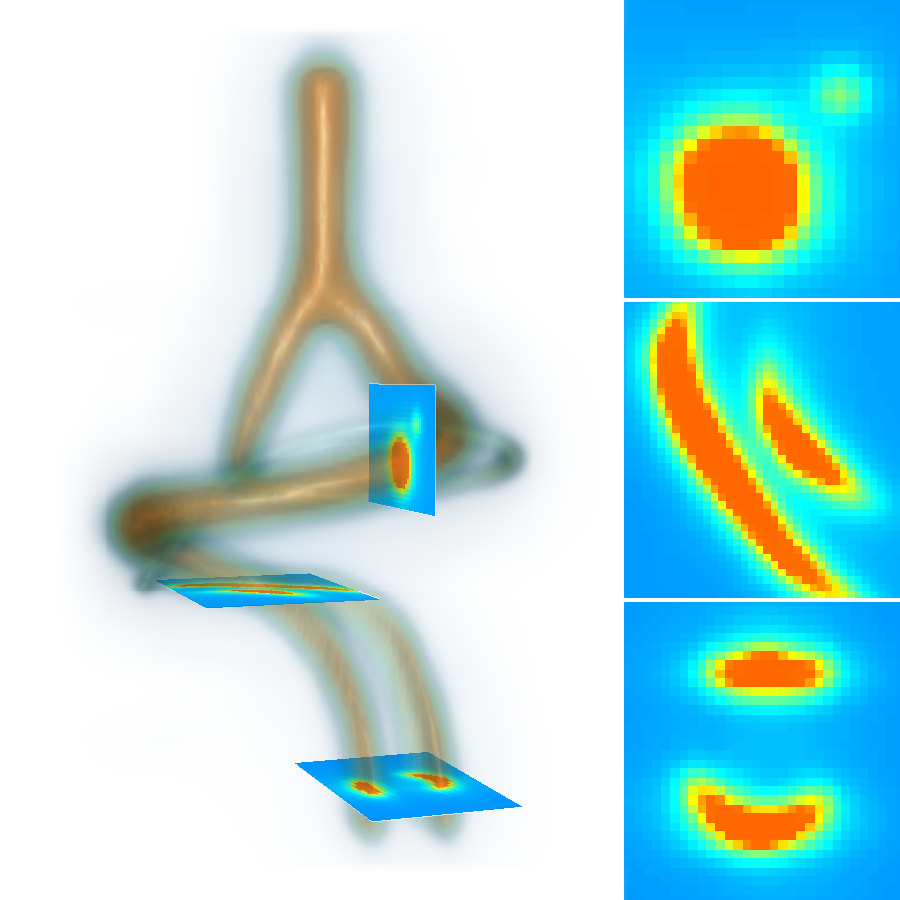

, , and modulate the respective components of the canonical Laplacian of Gaussian () filter oriented along the principal directions of . It is clear that given any arbitrary orientation as an orthonormal basis similar to , the proposed dictionary of filtering kernels can steer by computing the rotation transform, which maps the integral orientation basis of each Gaussian kernel on . Together with the SLoGS filtering kernel , we determine the second-moment matrix associated to the filter impulse response by adopting the ellipsoid model in the continuous neighborhood of . A symmetric tensor is derived from the eigendecomposition of as , where is the diagonal matrix representing the canonical unitary volume ellipsoid

the respective semiaxes’ lengths. Conversely from , which is indeterminate, the tensor field is a symmetric positive definite (SPD) matrix for any . Here, the definition of the tensor kernel in (4) can be further reformulated exploiting the intrinsic log-concavity of . By mapping , a convex quadratic form is obtained, so that is an SPD, as the modelled tensor . In either case, the manifold of tensors can be mapped into a set of 6 independent components in the Log-Euclidean space, which greatly simplifies the computation of Riemannian metrics and statistics. We refer to [3] for a detailed methodological description. The continuous and smooth tensor field inherits the steerable property. Similarly to diffusion tensor MRI, the kernel shows a preferred diffusion direction for a given energy potential, e.g. the scalar function itself (fig. 1). This allows to define an arbitrary dictionary of filtering kernels (DFK) that embeds anisotropy and high-order directional features to scalar curvilinear templates, which enhances and locally resembles typical, smooth vessel patterns. Together with the arbitrary SLoGS DFK, we also introduce an extra pair of non-curvilinear kernels for completeness. These are the pseudo-impulsive , an isotropic derivative filter given by the Laplacian of Gaussian of , representing a Dirac delta function for . Also, the uniformly flat is another isotropic degenerate case, where the Laplacian of Gaussian derives from , which is assumed to be a uniform, constant-value kernel for . The purpose of introducing the extra kernels is to better contrast regions that most likely relate to vessel boundaries and to image background, respectively. Although and have singularities, ideally they represent isotropic degenerate kernels. Therefore we associate pure isotropic tensors for any given , so that (Identity). The respective directional kernel bases are undetermined.

The scalar vesselness responses of both HCP and PC images are determined using the state-of-the-art Frangi filter (FFR) [8], and Optimally Oriented Flux (OOF) [12]. Also, the connected vesselness map (CVM) and the associated tensor field (TF) are synthesized for the same dataset using VTrails. The connectedness of the considered scalar maps is qualitatively assessed and the TF is inspected as proof of concept in section 3.1.

3.1 Connectedness of the Vesselness Map

Fig. 3 shows the connectedness of vessels recovered from state-of-the-art vascular enhancers and curvilinear ridge detectors FFR and OOF together with the proposed CVM for the synthetic HCP and the real PC images.

On the synthetic phantom, FFR shows a fragmented and rough vesselness response in correspondence of irregularly shaped sections of the structure. Also, the response at the bifurcation is not smoothly connected with the branches (triangular loop). Conversely, OOF recovers the phantom connectedness at the branch-point, and the vesselness response is consistent along the tortuous curvilinear section, however ghosting artifacts are observed as the shape of the phantom becomes irregular (C-like) or differs from a cylindrical tube. Also, close convoluted structures, which change scale rapidly in the HCP, produce inconsistent responses of OOF (fig. 3). CVM shows here a strongly connected vesselness response in correspondence of both regular and irregular tubular sections, with local maxima at structures’ mid-line. The connectedness of the structures is emphasized regardless the complexity of the shape, and it resolves spatially the tortuous curvilinear ‘kissing vessels’ without additional ghosting artifacts, despite the smooth profile.

Similar results are observed on the PC dataset: FFR has a poor connected response in the noisy and low-resolution image. Vessels are overall enhanced, however thin and fragmented structures remain disconnected. Overall, the vesselness response is not uniform within the noisy structures, where maximal values are often off-centred. A more consistent response is obtained from OOF, where the connectedness of vessels is improved. Maximal response is observed at the mid-line of vessels, however, noise rejection is poor. CVM strongly enhances here the vessel connectivity. The fragmented vessels of PC have a continuous and smooth response in CVM with higher values and a more defined profile. Large vessels shows solid connected regions with local maxima at mid-line as in OOF. Conversely from OOF, CVM shows improved noise rejection in the background.

The respective tensor fields (TF) synthesized on both HCP and PC show consistent features. The TF’s characteristics are in line with the connectedness of CVM: enhanced and connected vessels are associated with high anisotropy, whereas background areas show a predominant isotropic component.